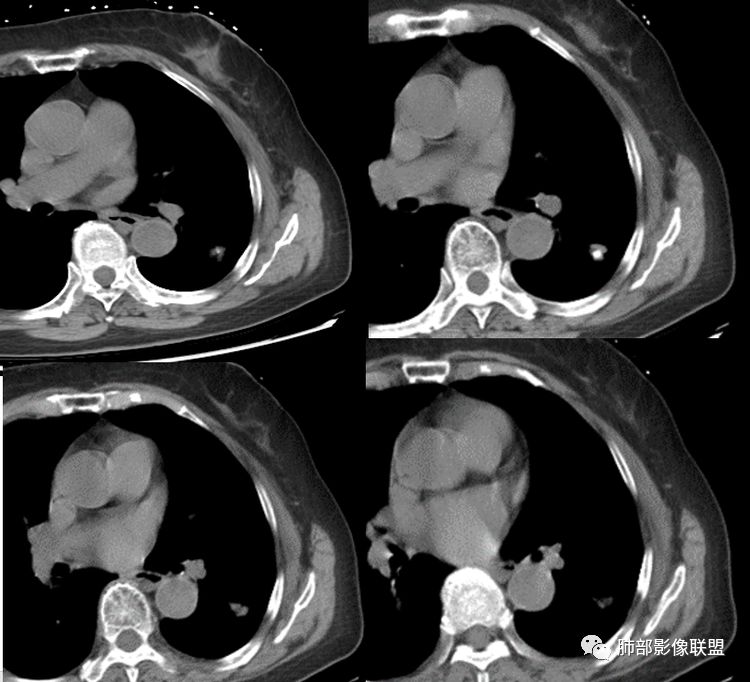

冠状薄层像是恶性南边:

结果:微浸润性腺癌

南边:这类病变,其实我们读了很多了。属于什么样的病变,属于瘢痕癌。我先标注给大家看一下,这个良恶性特点在哪里:

本例点评:

1.肺部结节多钙化,常常是良性病灶的象征之一。如结核、错构瘤等。肺癌钙化不多见,如小细胞肺癌的钙化椒盐样分布,转移瘤结节常随机且多发等等。

2.本例肺结节内部钙化影规整而密实,既不同于错构瘤的“爆米花”或“桑葚”铺展,又有别于结核球的典型的同心圆样排布。

3.如我们无视这一钙化灶,结节影却似乎表现出另一副面孔,实性成份较多,边缘不规则,居然有磨玻璃有分叶、有异常供血、有棘状突起有胸膜牵拉等。病灶孤立,不像错构瘤静悄悄悬挂血管旁,亦未如结核球那样多卫星灶。

4.注意增强扫描,实性部分有较明显强化,这无论在结核球或是错构瘤都非常少见。

5.肺部钙化灶原本常见。肺组织并不会因为局部钙化灶的存在而豁免新生物。